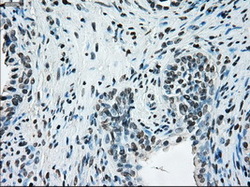

- Immunohistochemical staining of paraffin-embedded thyroid tissue using anti-ERCC1 mouse monoclonal antibody. (Dilution 1:50).